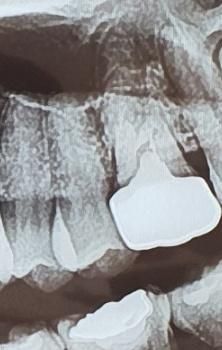

양쪽 어금니 임플란트 해야하는데 사진만으론 뼈이식을 해야하는지 알 수 없나요?

뼈이식하면 치료기간을 최소 6개월은 잡아야 할까요?

• 2번 째 사진

저정도 상태라면 뼈이식이 필요하진 않을것같고 뼈이식을 하더라도 식립하면서 뼈이식을 조금하면될것같습니다.

1. 네 섣불리 저거만 보고 판단하기엔 좀 그렇고, ct를 찍던가 아니면 수술하면서 직접 보고 판단합니다

2. 뼈이식 없이 했을때보다 조금 더 기간이 추가되긴 합니다만 기간이 얼마나 걸린다 단정지을 수 없습니다.

뼈이식을 많이 하지는 않고 조금 하면 될 것 같습니다. 6개월 정도면, 마무리될 듯 합니다.